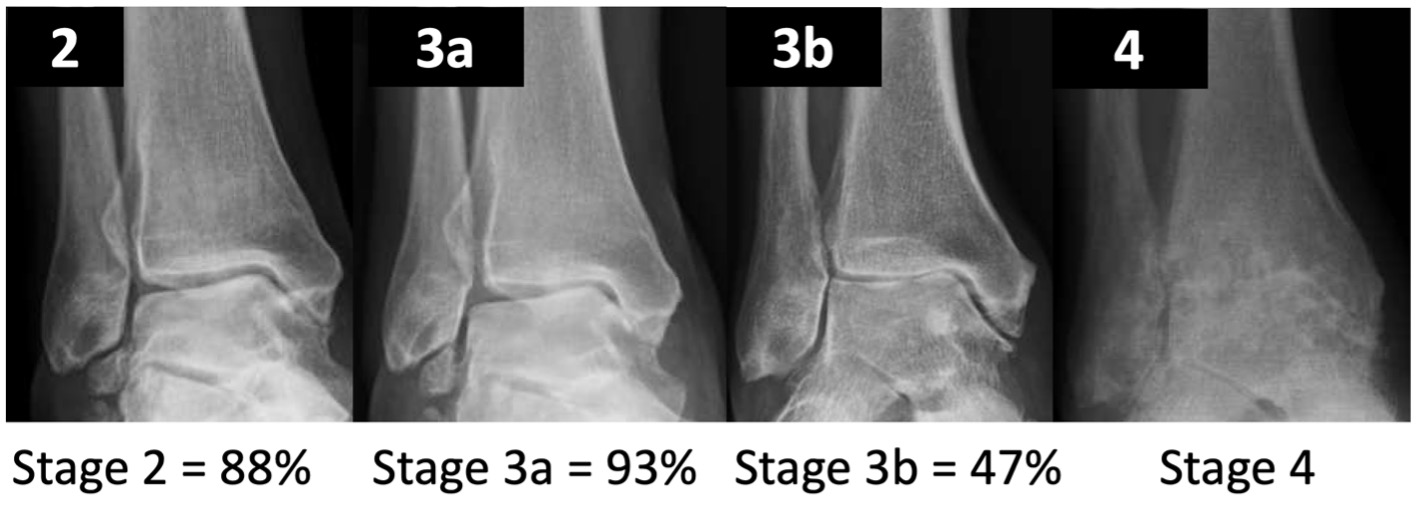

- increasing levels of arthritis (Takakura grade) lead to higher 5y failure rate (defined as conversion to ankle arthrodesis or replacement)

- significantly higher failure rate from grade 3a to 3b

- 3a where obliteration of the joint space is limited to the gutter

- 3b where obliteration of the joint space extends to the roof of the talar dome

Figure 4. 5-year failure rate of SMO (conversion to TAR or AA)